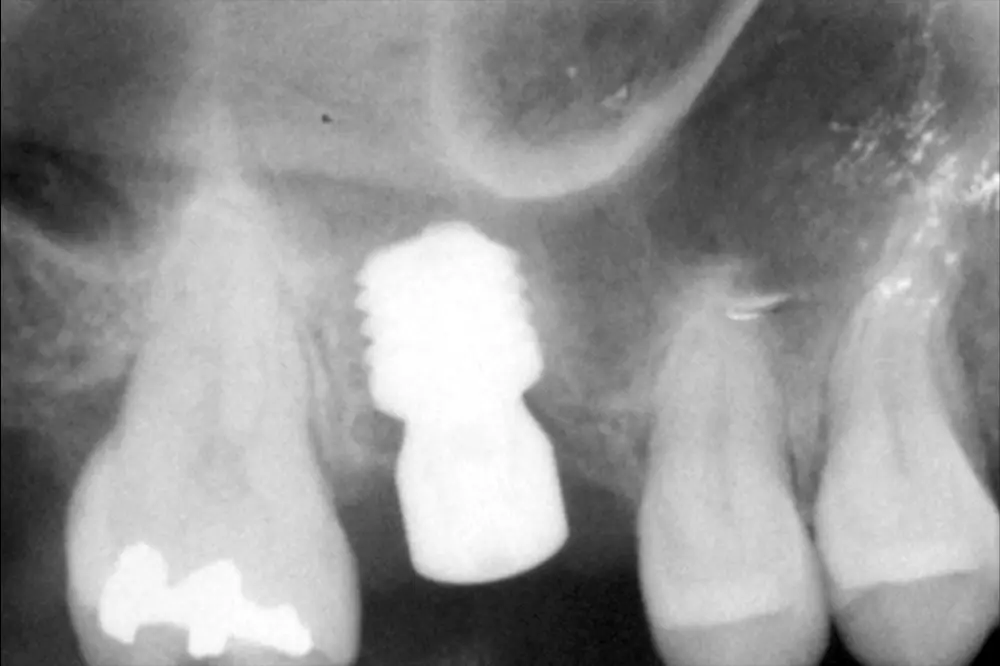

Fig. 7. Radiografía postquirúrgica con el implante en una fase con el pilar de cicatrización.

En este punto se planifica la extracción del implante de 4,5 mm de longitud y la inserción de un implante de 6,5 mm, que será un mejor candidato al mantenimiento óseo y al comportamiento biomecánico correcto al ser una carga unitaria (fig. 6). El implante es retirado a contratorque mediante un conector directo de forma totalmente atraumática y en el mismo lecho, sin fresado, se realiza la inserción del segundo implante (6,5 mm de longitud), que como se inserta con un buen torque (40 Ncm) se deja en una sola fase, con el transepitelial unitario (Unit®) y su tapa de protección (fig. 7)